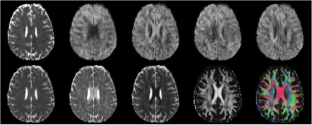

Fig. 1

Fig. 2

Fig. 3

Fig. 4

Fig. 5

Fig. 6

Fig. 7

Fig. 8

Data for Fig. 8 were provided by the Human Connectome Project, WU-Minn Consortium (Principal Investigators: David Van Essen and Kamil Ugurbil; 1U54MH091657) funded by the 16 NIH Institutes and Centers that support the NIH Blueprint for Neuroscience Research; and by the McDonnell Center for Systems Neuroscience at Washington University. Christophe Lenglet, PhD processed the HCP data.